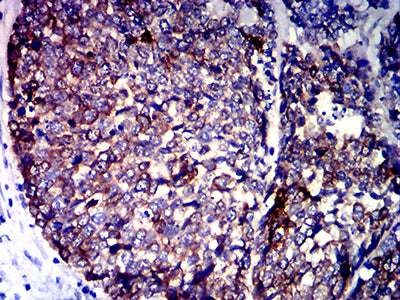

分类: 科研抗体货号: 32039别名: ILT3; LIR5; LILRB4; ILT-3; LIR-5应用: IHC,IF,FCM反应种属: Human